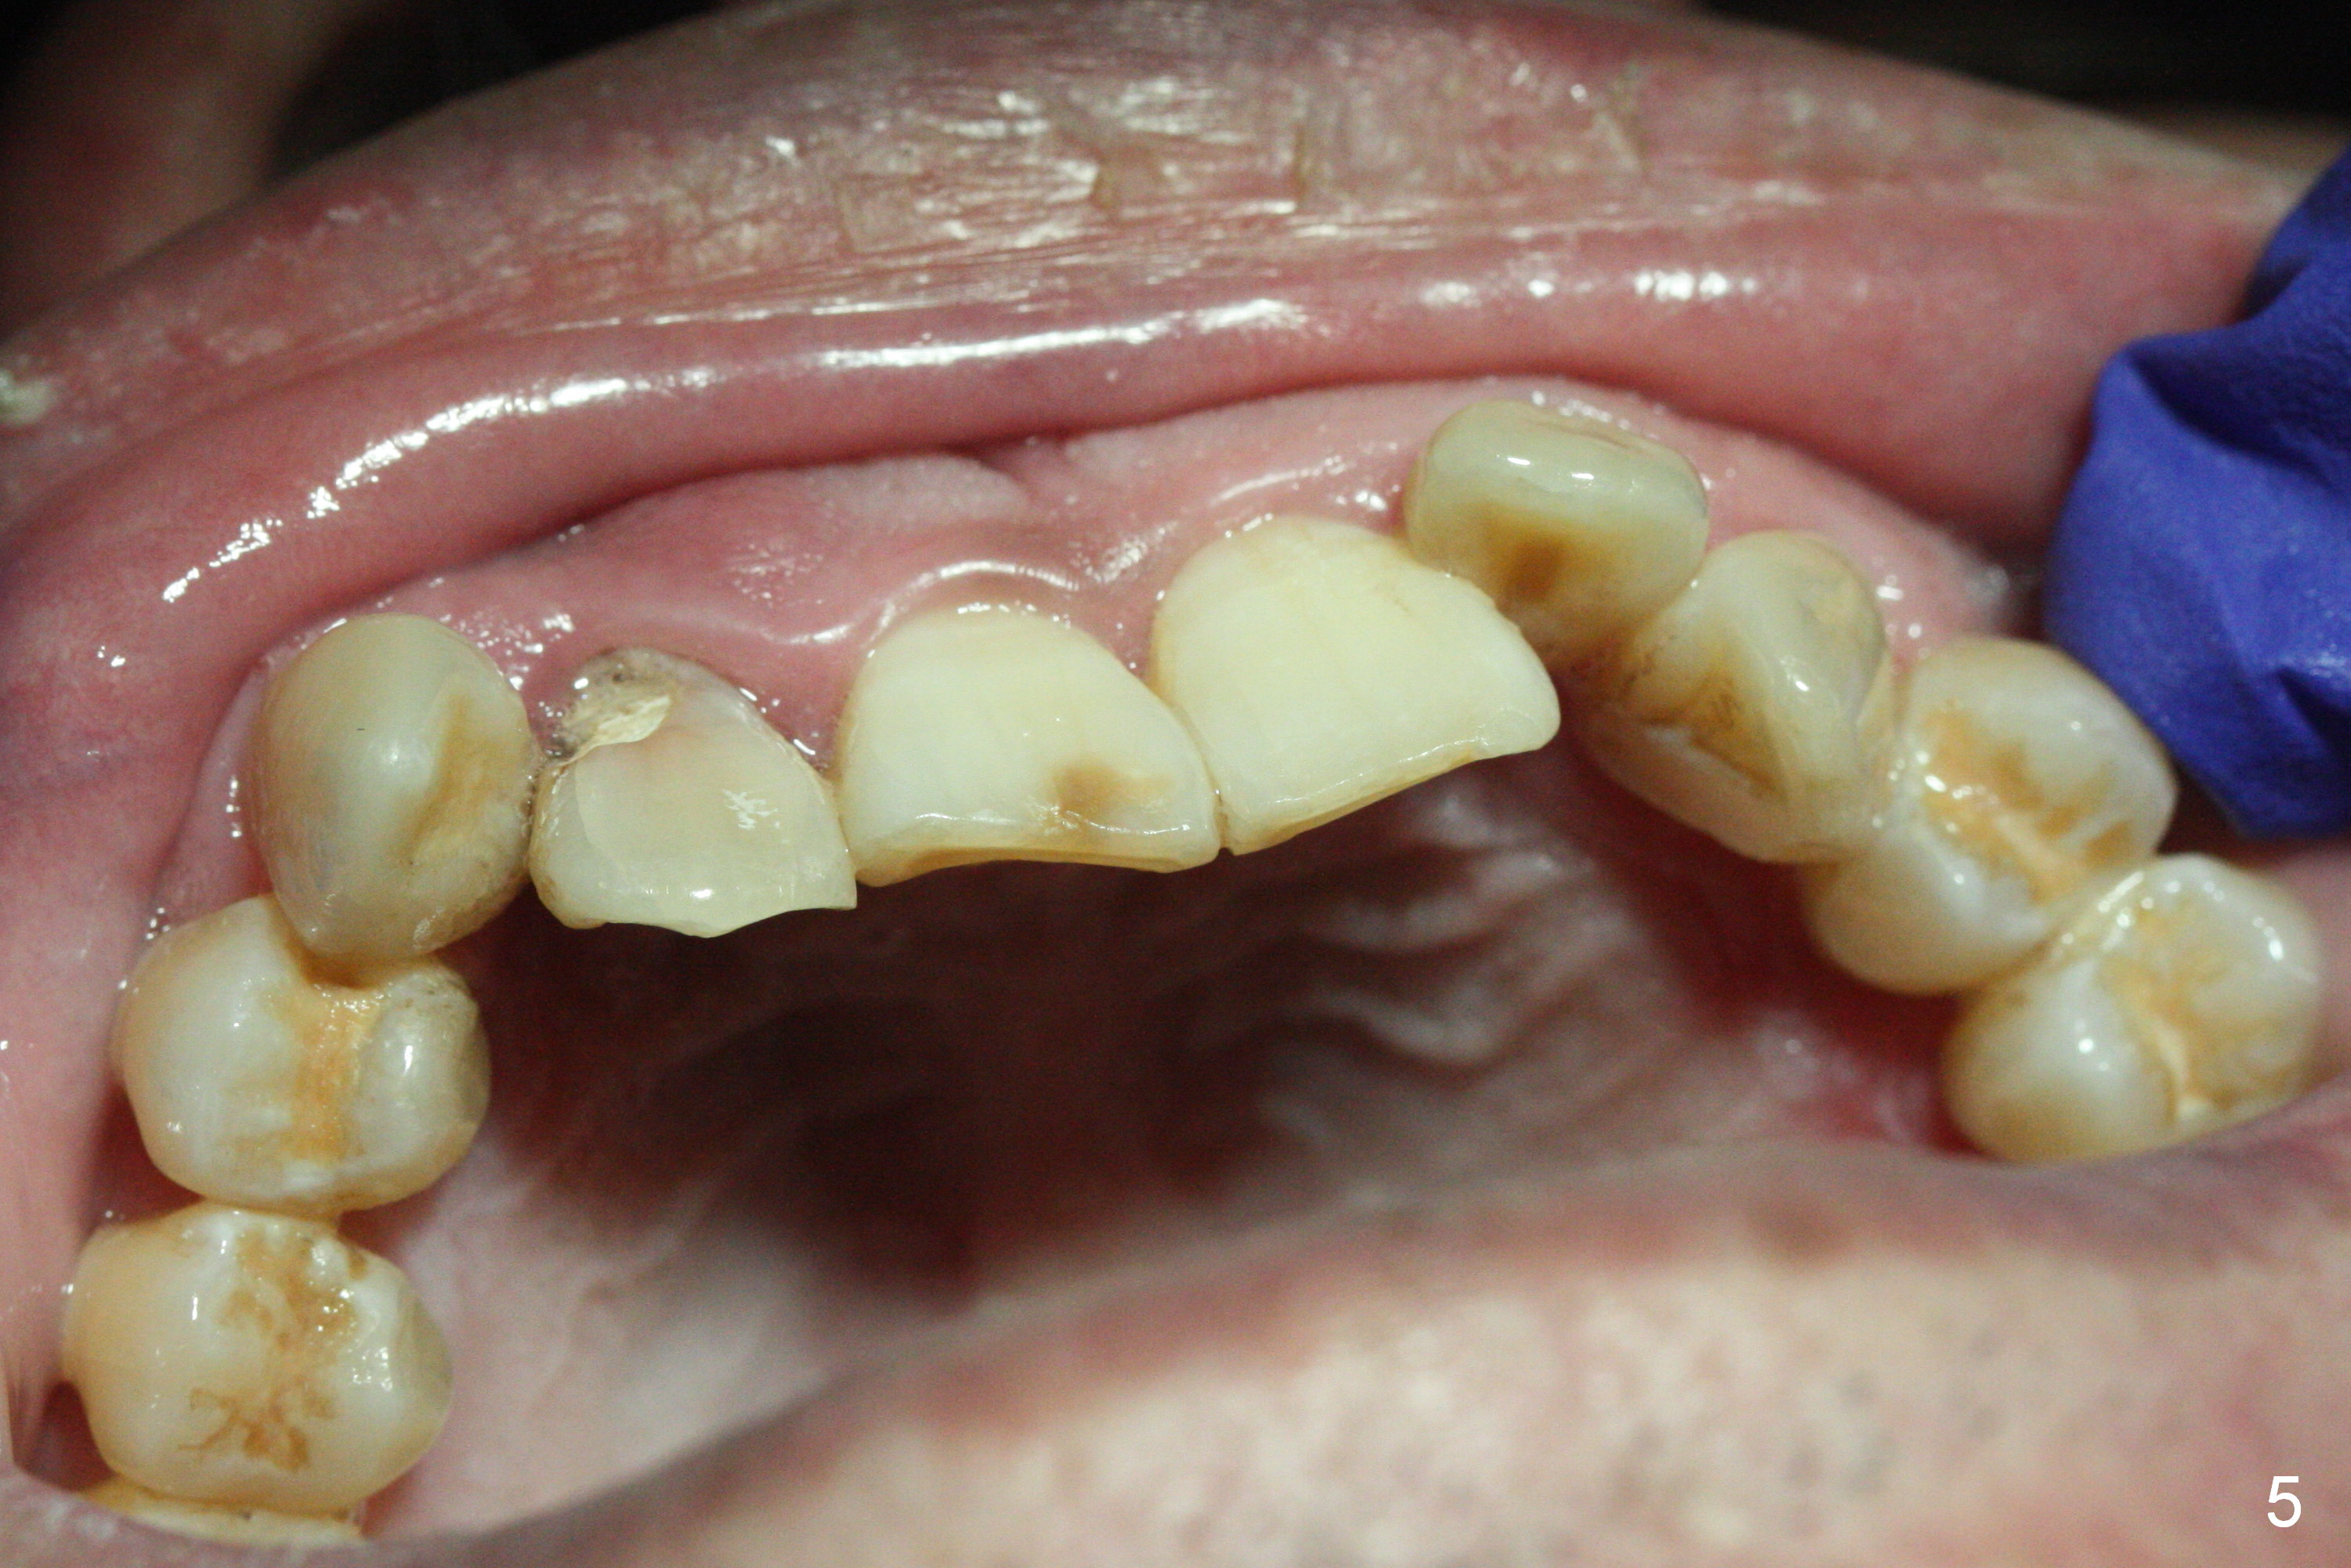

A 52-year-old man had a non-restorable lateral incisor 3 years ago (Fig.1). It fractures lately (Fig.2) with a buccal abscess (Fig.3 *) ) and fistula (>, possible severe buccal plate defect, prepare PRF). Severe deep bite (Fig.4) and malocclusion (Fig.5) will present a challenge to implant provisional restoration.

If the deep bite is a problem, place a healing abutment or the immediate provisional without the palatal apical wall. Or ask the patient in advance whether the right lateral can be placed as labial as the tooth #10 or not (Fig.3-5).